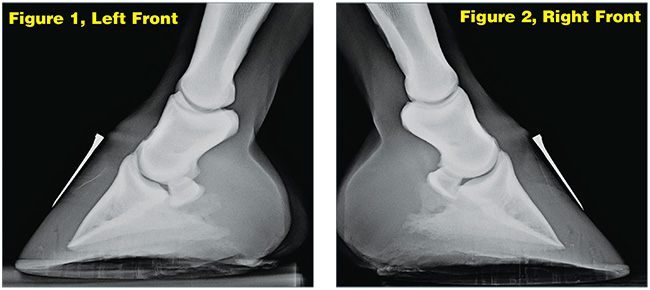

However, Junior did not improve in the following days. Instead, he continued to worsen, as evidenced by his shifting back and forth on his front feet. Fearing laminitis, Gindlesperger shot a series of radiographs (Figures 1 and 2) on Dec. 20, 2010.